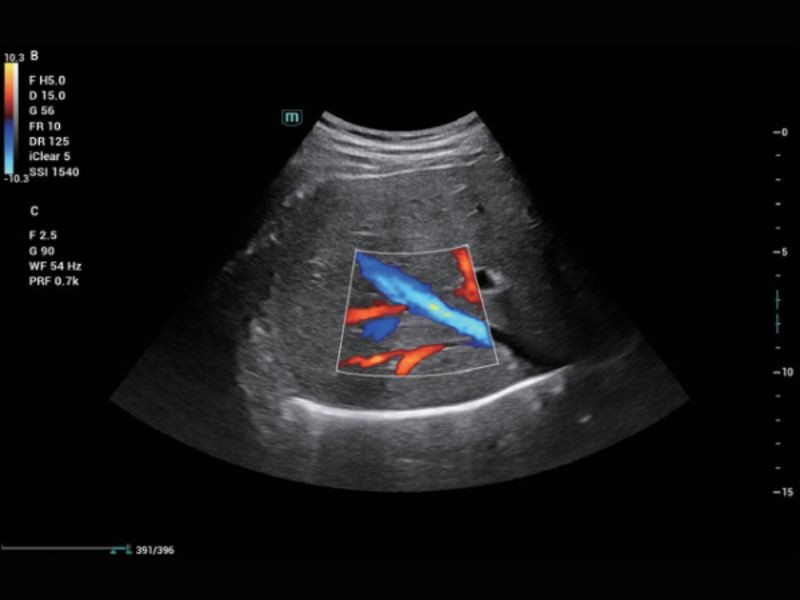

Soluções de imagem abrangentes com tecnologia ZST +

A plataforma ZST + é uma inovação extraordinária, representando uma evolução do ultrassom. Transformando métricas de ultrassom de formação de feixe convencional para processamento baseado em dados de canal. Ela supera a limitação tradicional de trade-off entre resolução espacial, resolução temporal e uniformidade de tecido, fornecendo qualidade de imagem excepcional para soluções de imagem infinitas com melhorias ininterruptas.